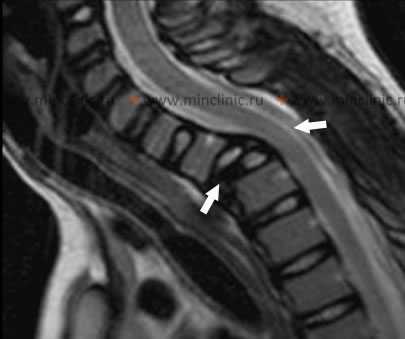

При МРТ шейного отдела позвоночника на изображении с боку можно увидеть смещение тела C7 позвонка и перелом тела Th1, образующее сдавление спинного мозга на этом уровне после травмы (указаны стрелками).